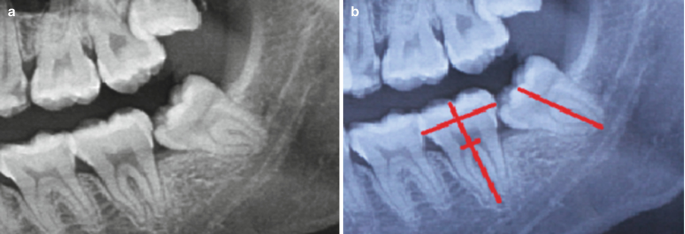

사랑니 중에서도 똑바로 난 사랑니는 비교적 괜찮아요. 하지만 반쯤 나오거나 누워서 나오거나 하는 경우에는 충치 발생 위험이 훨씬 더 커집니다. 환자분 본인이 이런 형태 사랑니를 가지고 계시다면 특히나 더 관리를 잘해주셔야 하구요, 발치를 하시는것도 현명한 선택입니다. (출처: https://link.springer.com/)

사랑니의 ‘각도’가 옆 치아 손상 여부를 결정하는 중요한 요소입니다